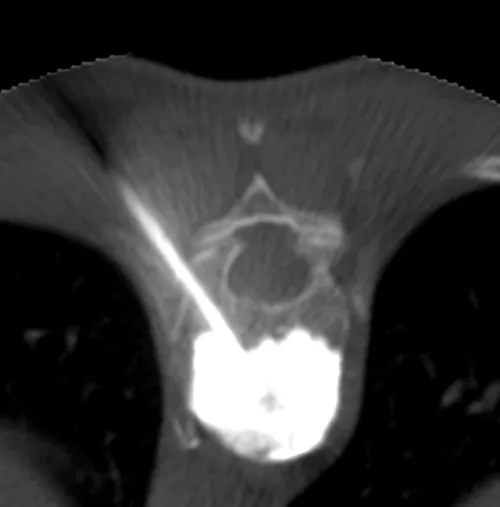

1. Trocard — 2. Ciment dans le corps vertébral